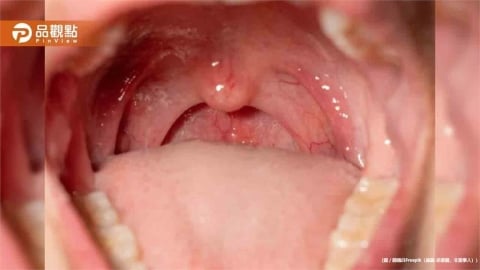

手機2分鐘揪口腔癌!台大AI快篩準確率破95% 2027年臨床應用